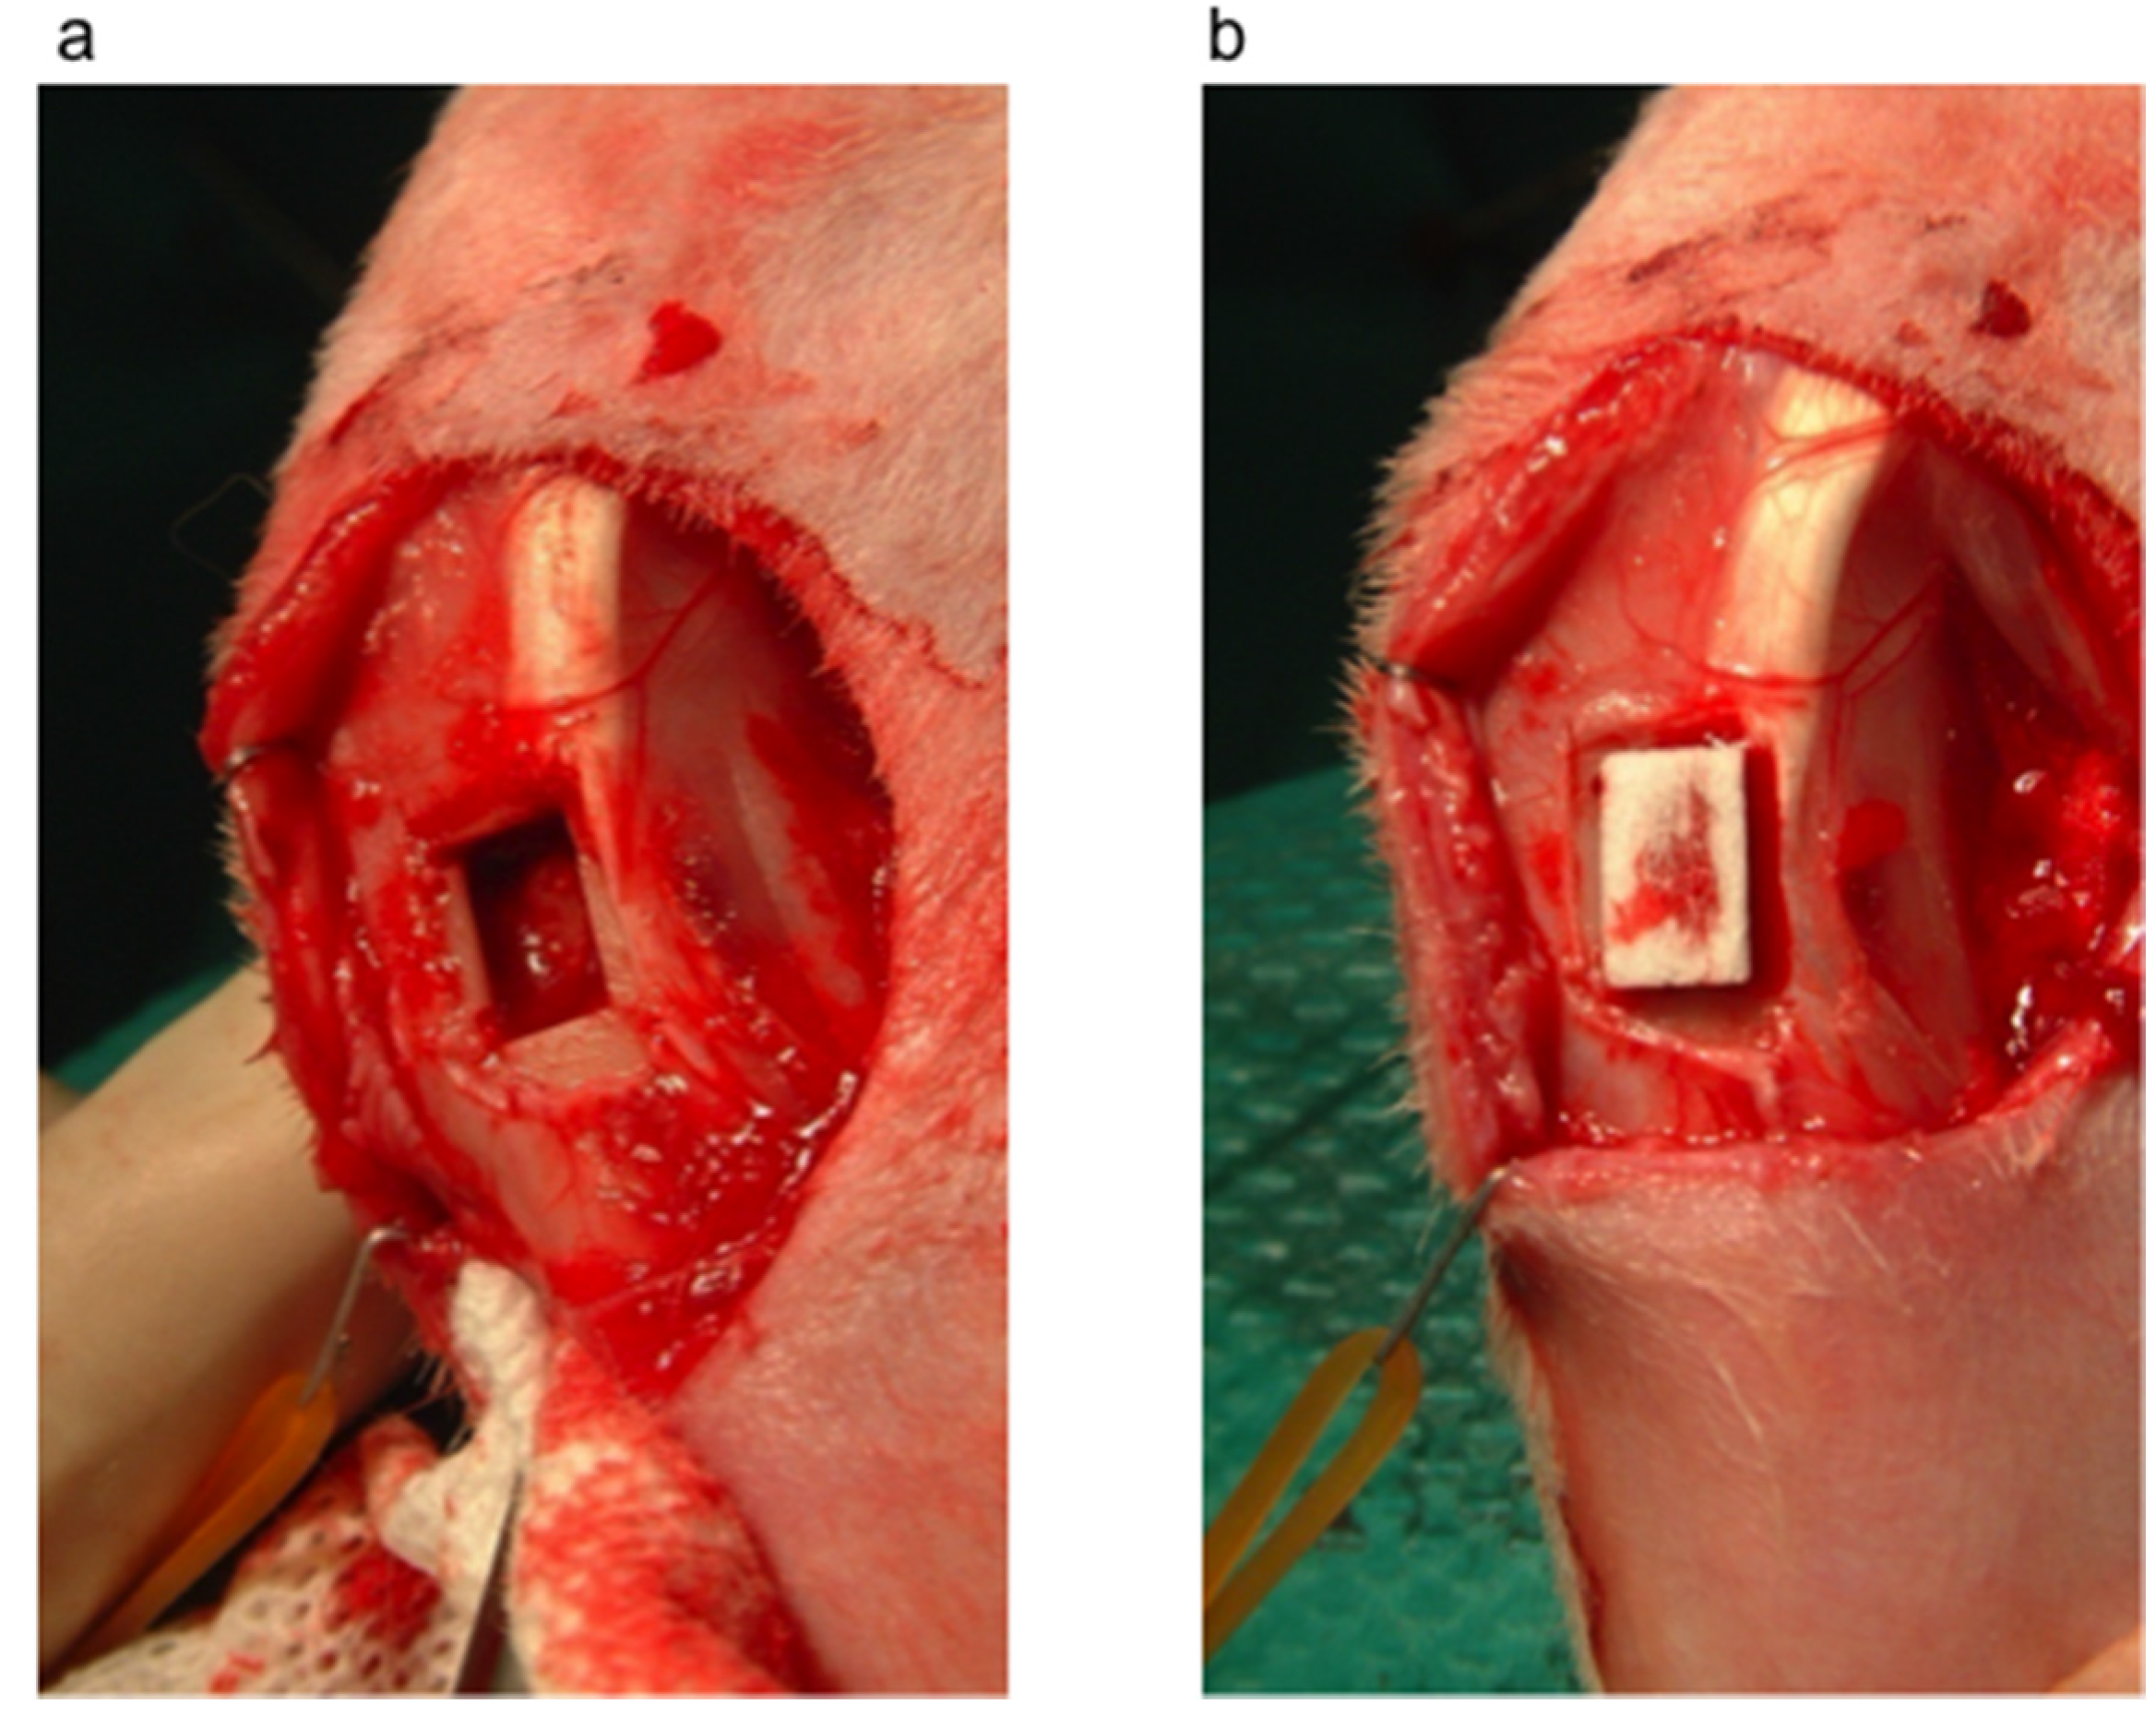

3.1. Bone Defect Animal Model